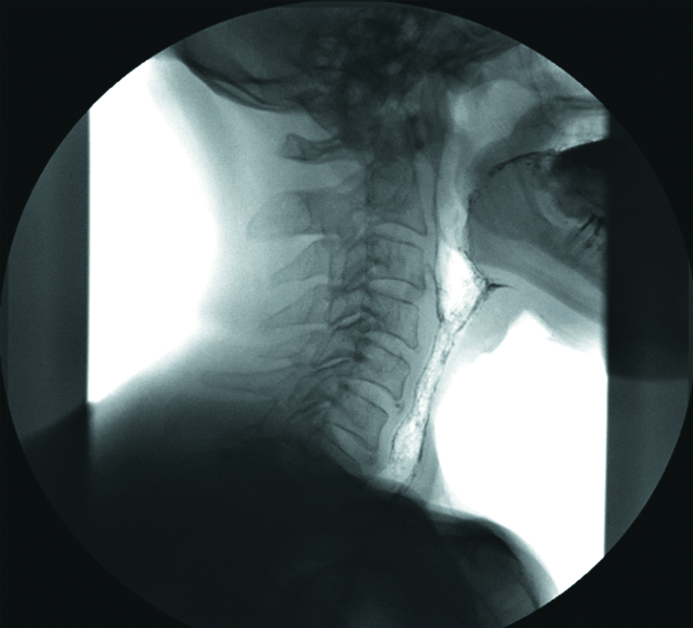

Control fluoroscopy of the cervical esophagus 4 months after the reconstructive stage did not detect filling defect or stenosis in the areas of the formed anastomoses between the pharynx and the flap or the esophagus and the flap (Figs. 8 and 9).

Figure 8. The X-ray image of the cervical esophagus. Front side

Рисунок 8. Рентгенография шейного отдела пищевода. Прямая проекция.

Figure 9. The X-ray image of the cervical esophagus. Lateral side

Рисунок 9. Рентгенография шейного отдела пищевода. Боковая проекция.